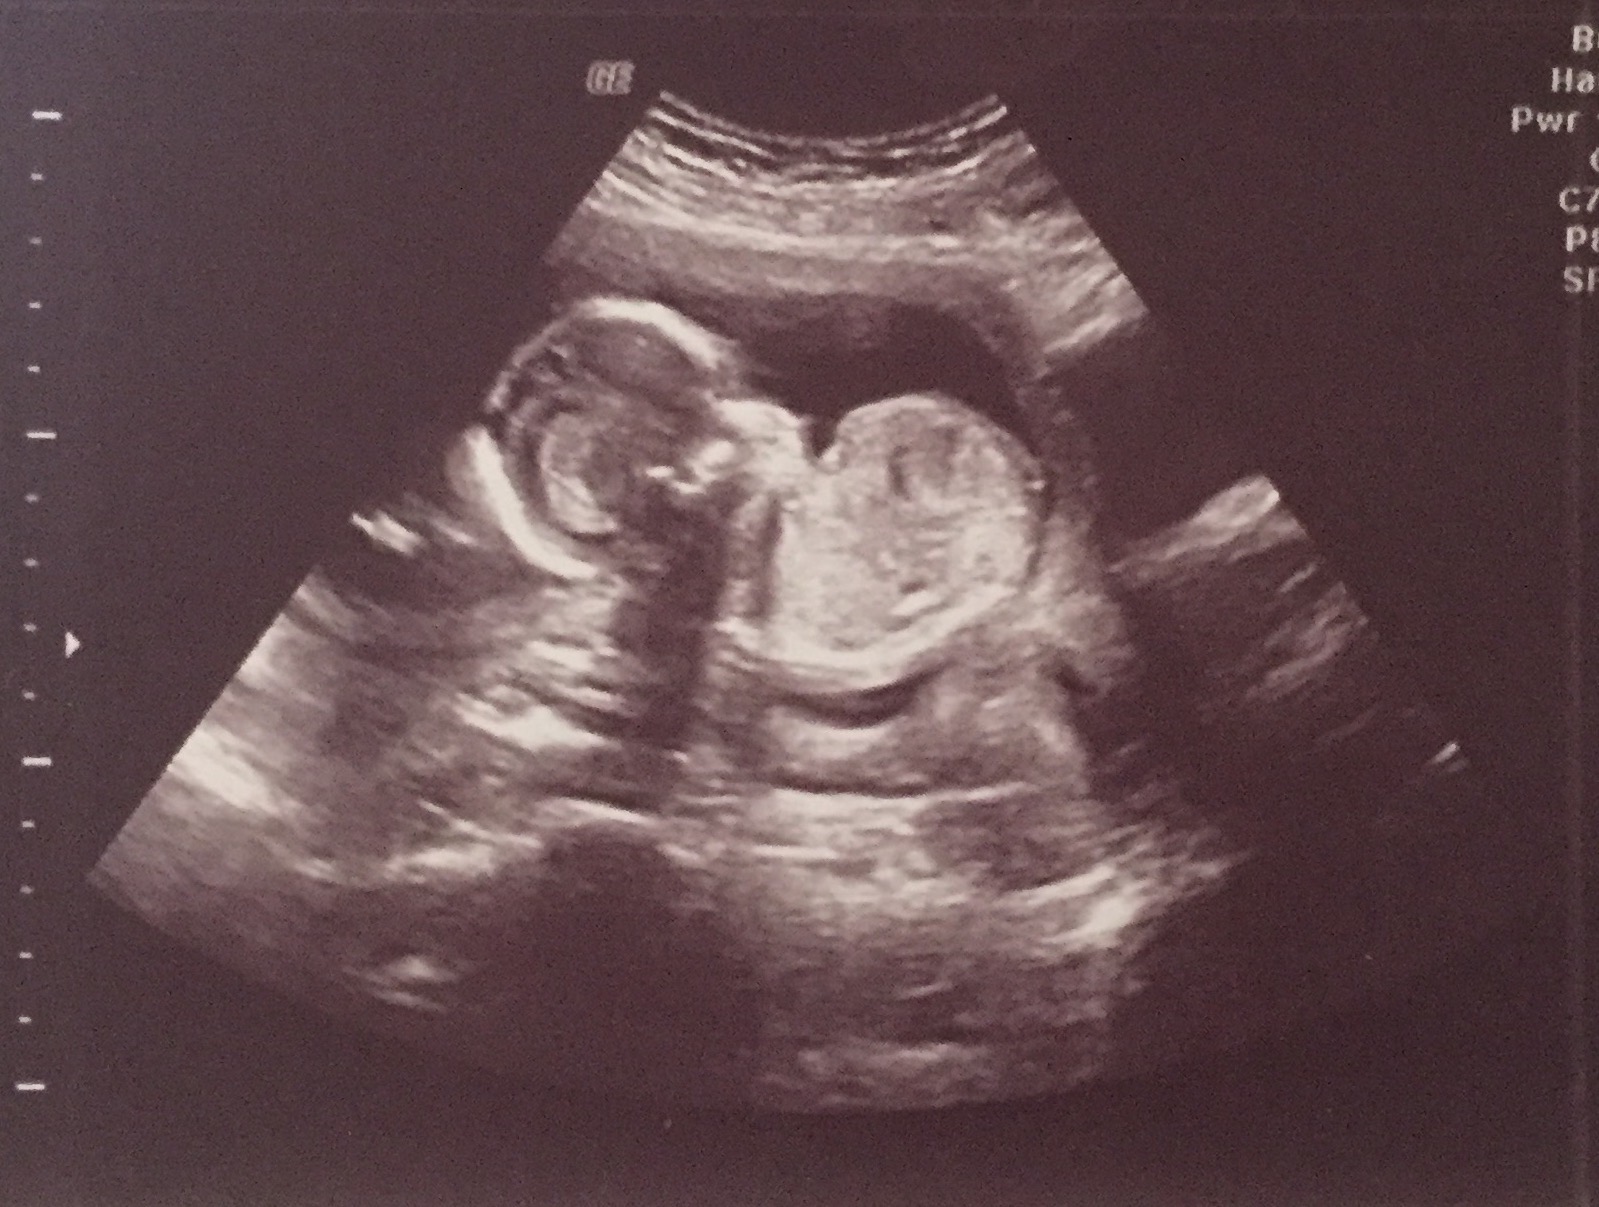

I had an elective 2d/4d ultrasound done at 16 weeks and 3 days to determine the gender of my baby. The baby wasn't all that cooperative and had the umbilical cord between its legs. It moved it's legs for a second and the ultrasound technician said that she saw the "hamburger buns" (labia). She also said that she saw the three white lines of the vaginal bones multiple times and that she felt confidant it was a girl. However, she could not get me a clear picture of the genitals in 3d because the baby would not move it's leg again to give a clear view of it's parts. She took this picture (1st picture) in 2d of what is the supposed white lines. I am just looking for opinions on whether this looks like a baby girl or if it could be a boy because I don't want to tell my whole family and then be surprised at my 19 week scan when they say it's a boy. The pictures are big, I'm not sure how to make them smaller.

Attachment 35761